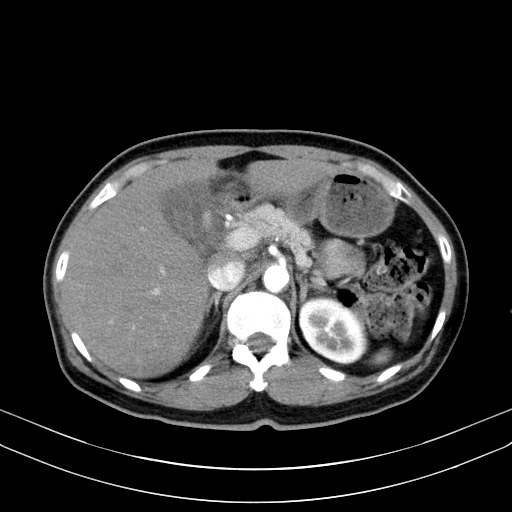

왼쪽 영상이 arterial phase, 오른쪽 위는 portal phase, 마지막으로 오른쪽 아래 영상이 delayed phase 영상입니다. arterial phase에서도 어느정도 조영증강이 되어 주변의 간실질과 비슷한 감쇄도를 보이고 있습니다. 다만, portal 및 delayed phase에서 조영제가 완전히 빠져나가 뚜렷한 저음영으로 보이는 wash-out 양상을 보이지 않고 조영제가 병변 안에 어느정도 머물러 있습니다.

이러한 양상으로 볼 때 간세포암보다는 이형성 결절(dysplastic nodule)일 가능성이 커 보이므로 초음파영상을 통한 추적관찰을 하게 된 케이스입니다.